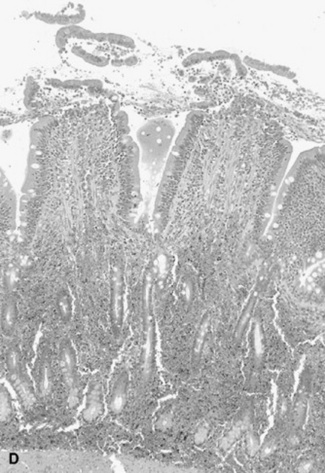

Abdominal radiography is useful to evaluate the small and large intestines for sand accumulation, enterolithiasis, impactions, or small intestinal disorders in foals. When sand is ingested, it generally will accumulate within the large colon along the ventral abdomen8 (Fig. 32-4). Radiography has been found to be a useful method to monitor the resolution of sand impactions after medical management; however, sequential examinations are needed to verify that the volume of sand has reduced.8 If the volume of sand is large enough, it is difficult to determine if an enterolith is present because of summation of the two lesions. Enteroliths are a solid concretion of mineral that usually forms around a nidus, such as a metallic foreign body (Fig. 32-5). The mineral composition is varied, as illustrated by the different opacities present within the enterolith. Radiographs have a 96.4% positive predictive value to detect enteroliths in high-prevalence areas. These enteroliths were generally found to be within the midabdominal radiograph, and 67% of small colon enteroliths caused large colon distention, which was also identified on radiographs.7 Impactions are more difficult to diagnose because usually there is just increased feed accumulation within the abdomen. Although no enterolith or obstruction is identified, granular material can be seen, usually within the ventral colon near the sternal flexure. This is because pelvic flexure impactions will cause the feed material to accumulate orad, causing distention of the left ventral colon (Fig. 32-6). Intestinal disorders such as functional ileus secondary to enteritis (Fig. 32-7) or obstruction secondary to intussusception or meconium impaction (Fig. 32-8) in foals can also be identified on abdominal radiographs. These images show large dilation of the small intestine, and differentiation between functional and mechanical ileus in foals is generally based on the size of the intestine and the volume of gas that is present.9 Evaluation of the abdomen using ultrasound may aid in qualifying the small or large intestinal motility as well as identifying the source of an obstruction if the determination on radiographs cannot be made.

image

Fig. 32-4 Standing lateral radiograph of a 4-year-old Arab mare with a history of colic. Note the large amount of opaque material within the ventral colon, likely secondary to sand accumulation.